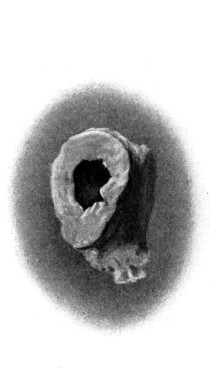

| 38 A and B. To illustrate the probable source of profuse hæmorrhage from the ear | 97 |

| 61. A case of traumatic orbital aneurysm | 207 |